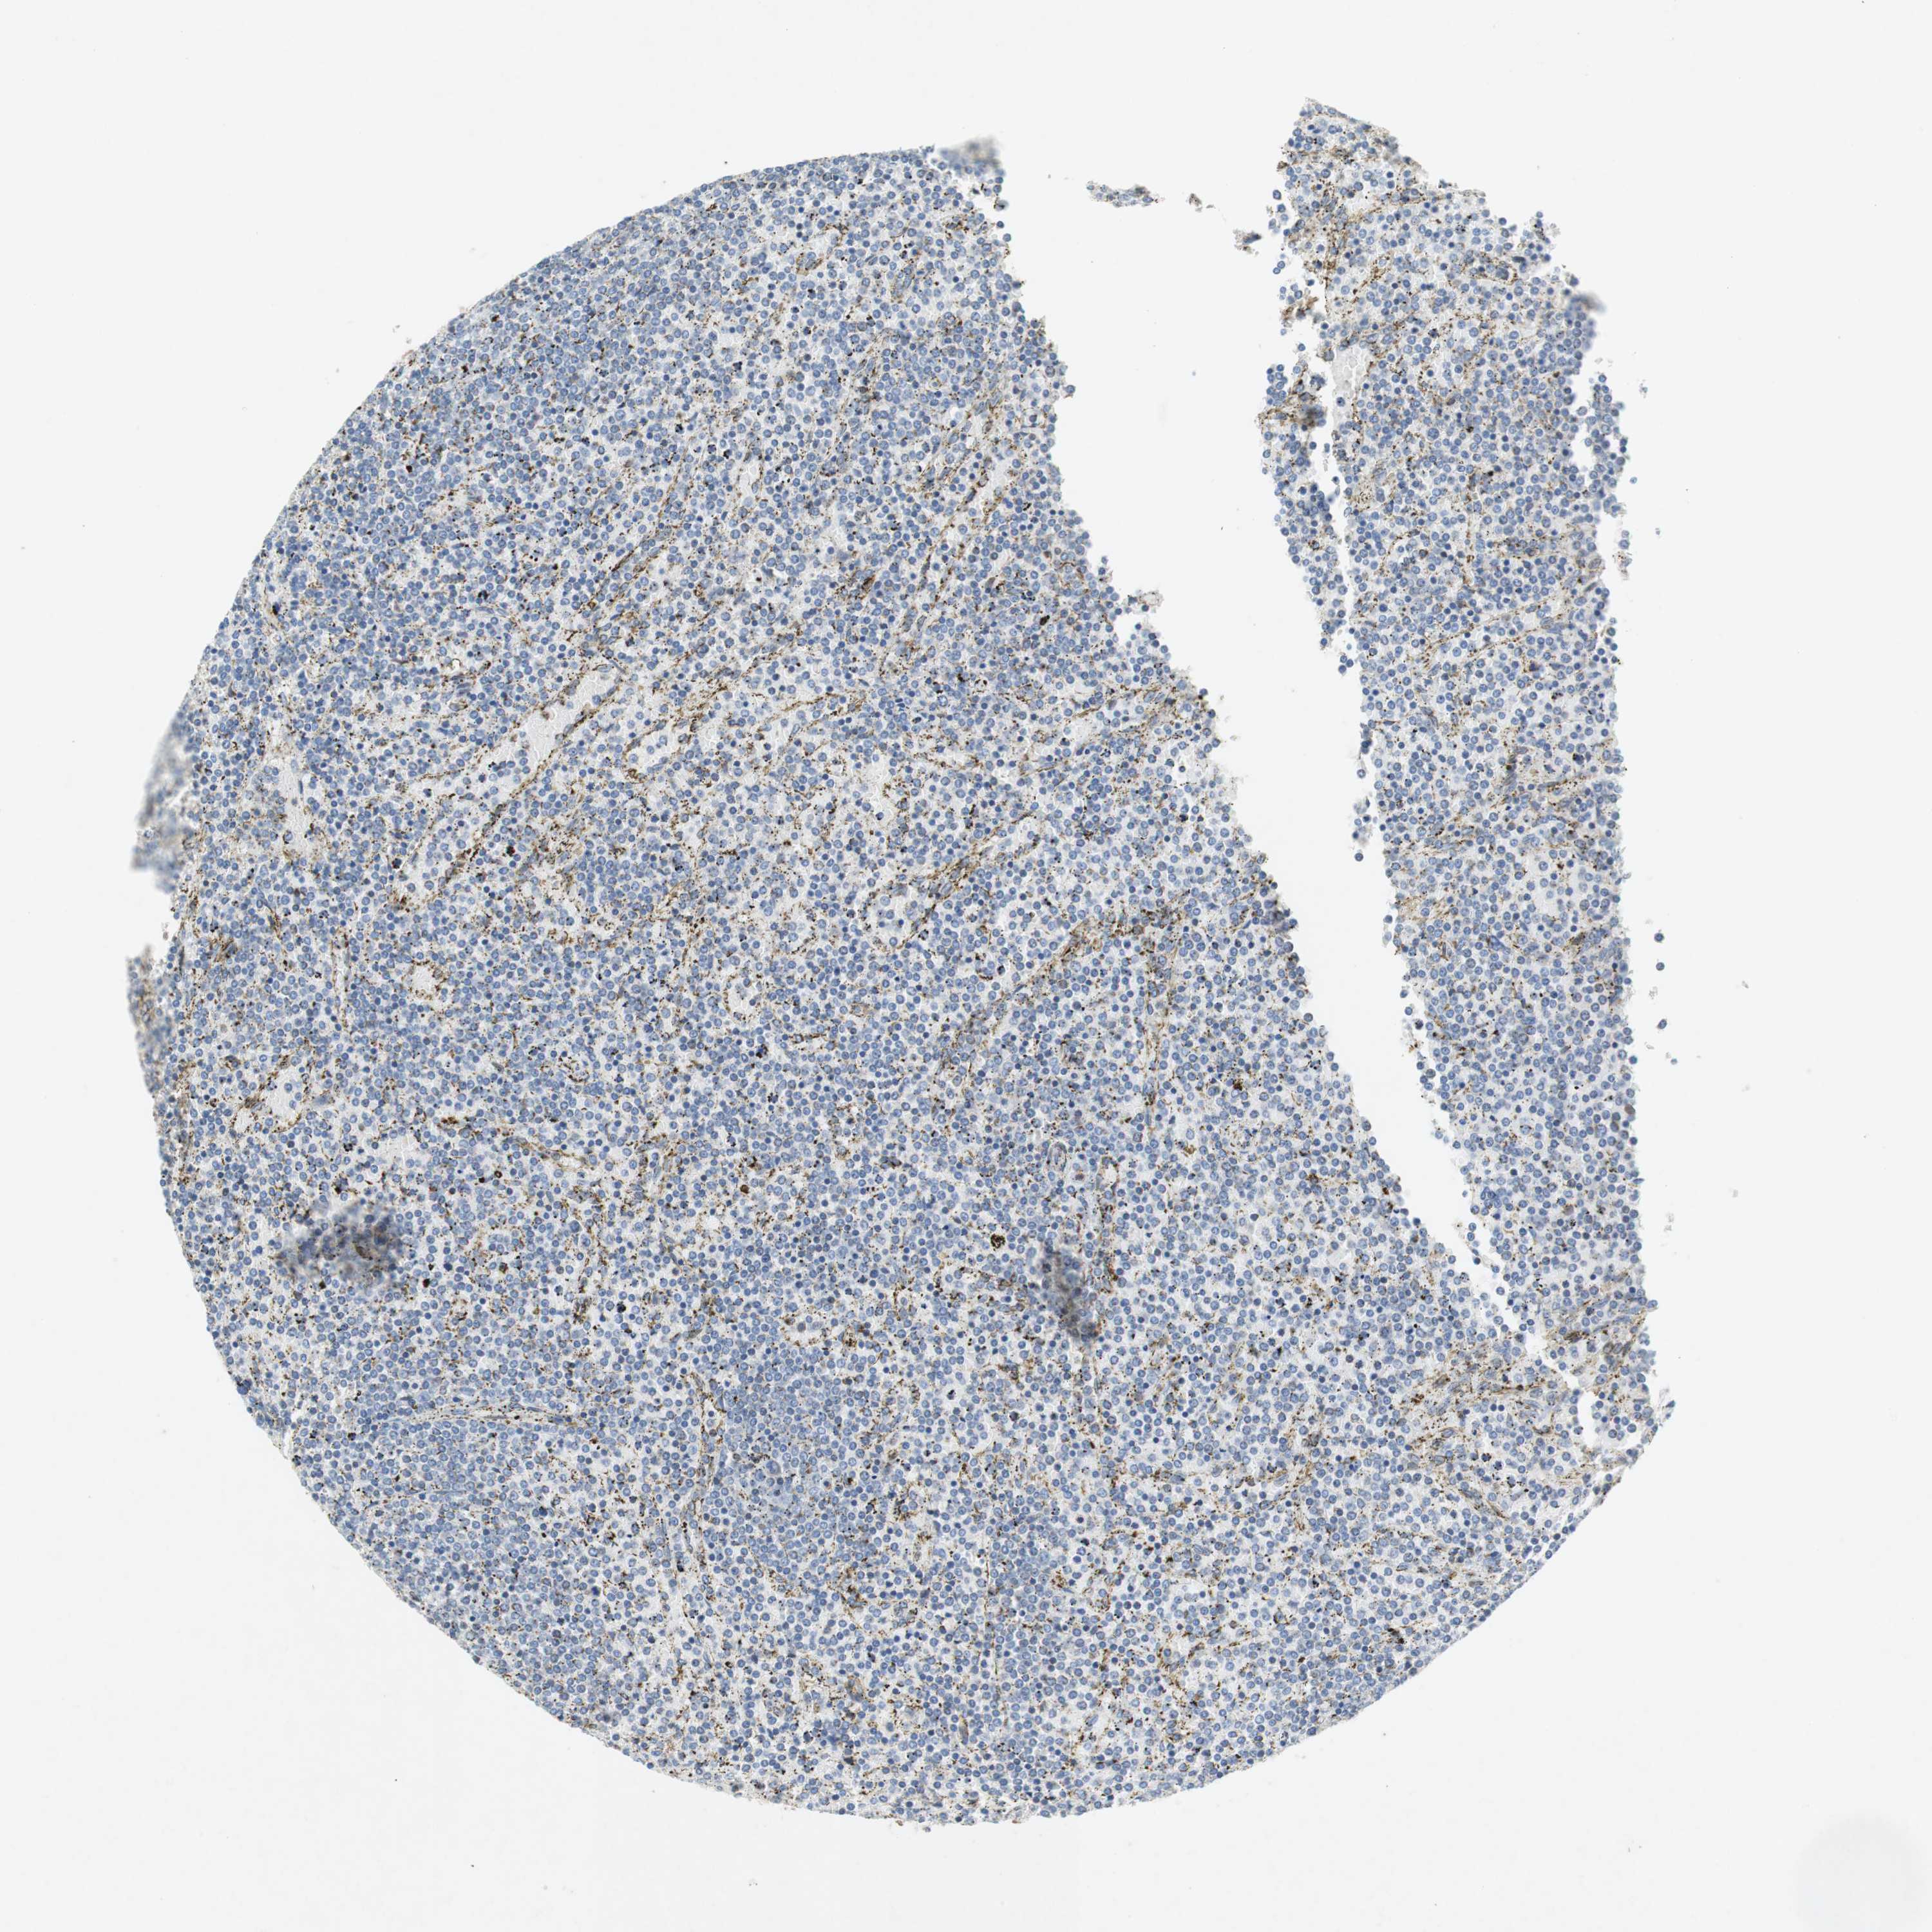

CANCER LYMPHOMA Show tissue menu

LYMPHOMA - Protein expressioni

A mouse-over function shows sample information and annotation data. Click on an image to view it in a full screen mode. Samples can be filtered based on level of antibody staining by selecting one or several of the following categories: high, medium, low and not detected. The assay and annotation is described here.

Each image is clickable and will lead to virtual microscopy that enables deeper exploration of all samples and also displays staining intensity scores, fraction scores and subcellular localization as well as patient and tissue information for each sample.

Antibody CAB005081

Malignant lymphoma, non-Hodgkin's type, High grade

Hodgkin's disease, NOS

Malignant lymphoma, non-Hodgkin's type, Low grade